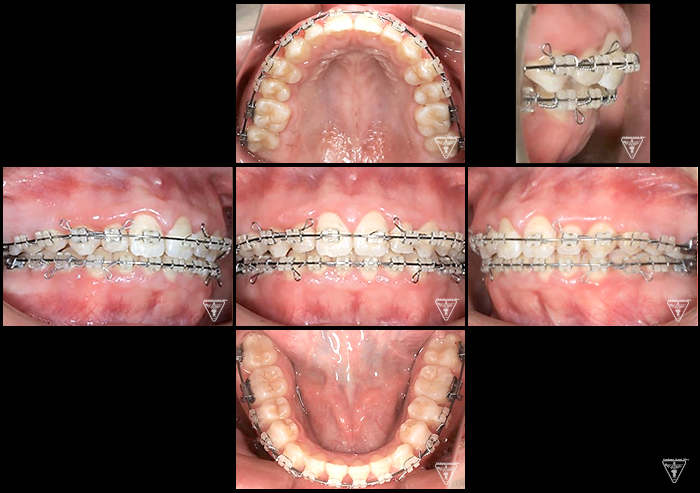

矯正器具 装着時の治療過程

初期

後期